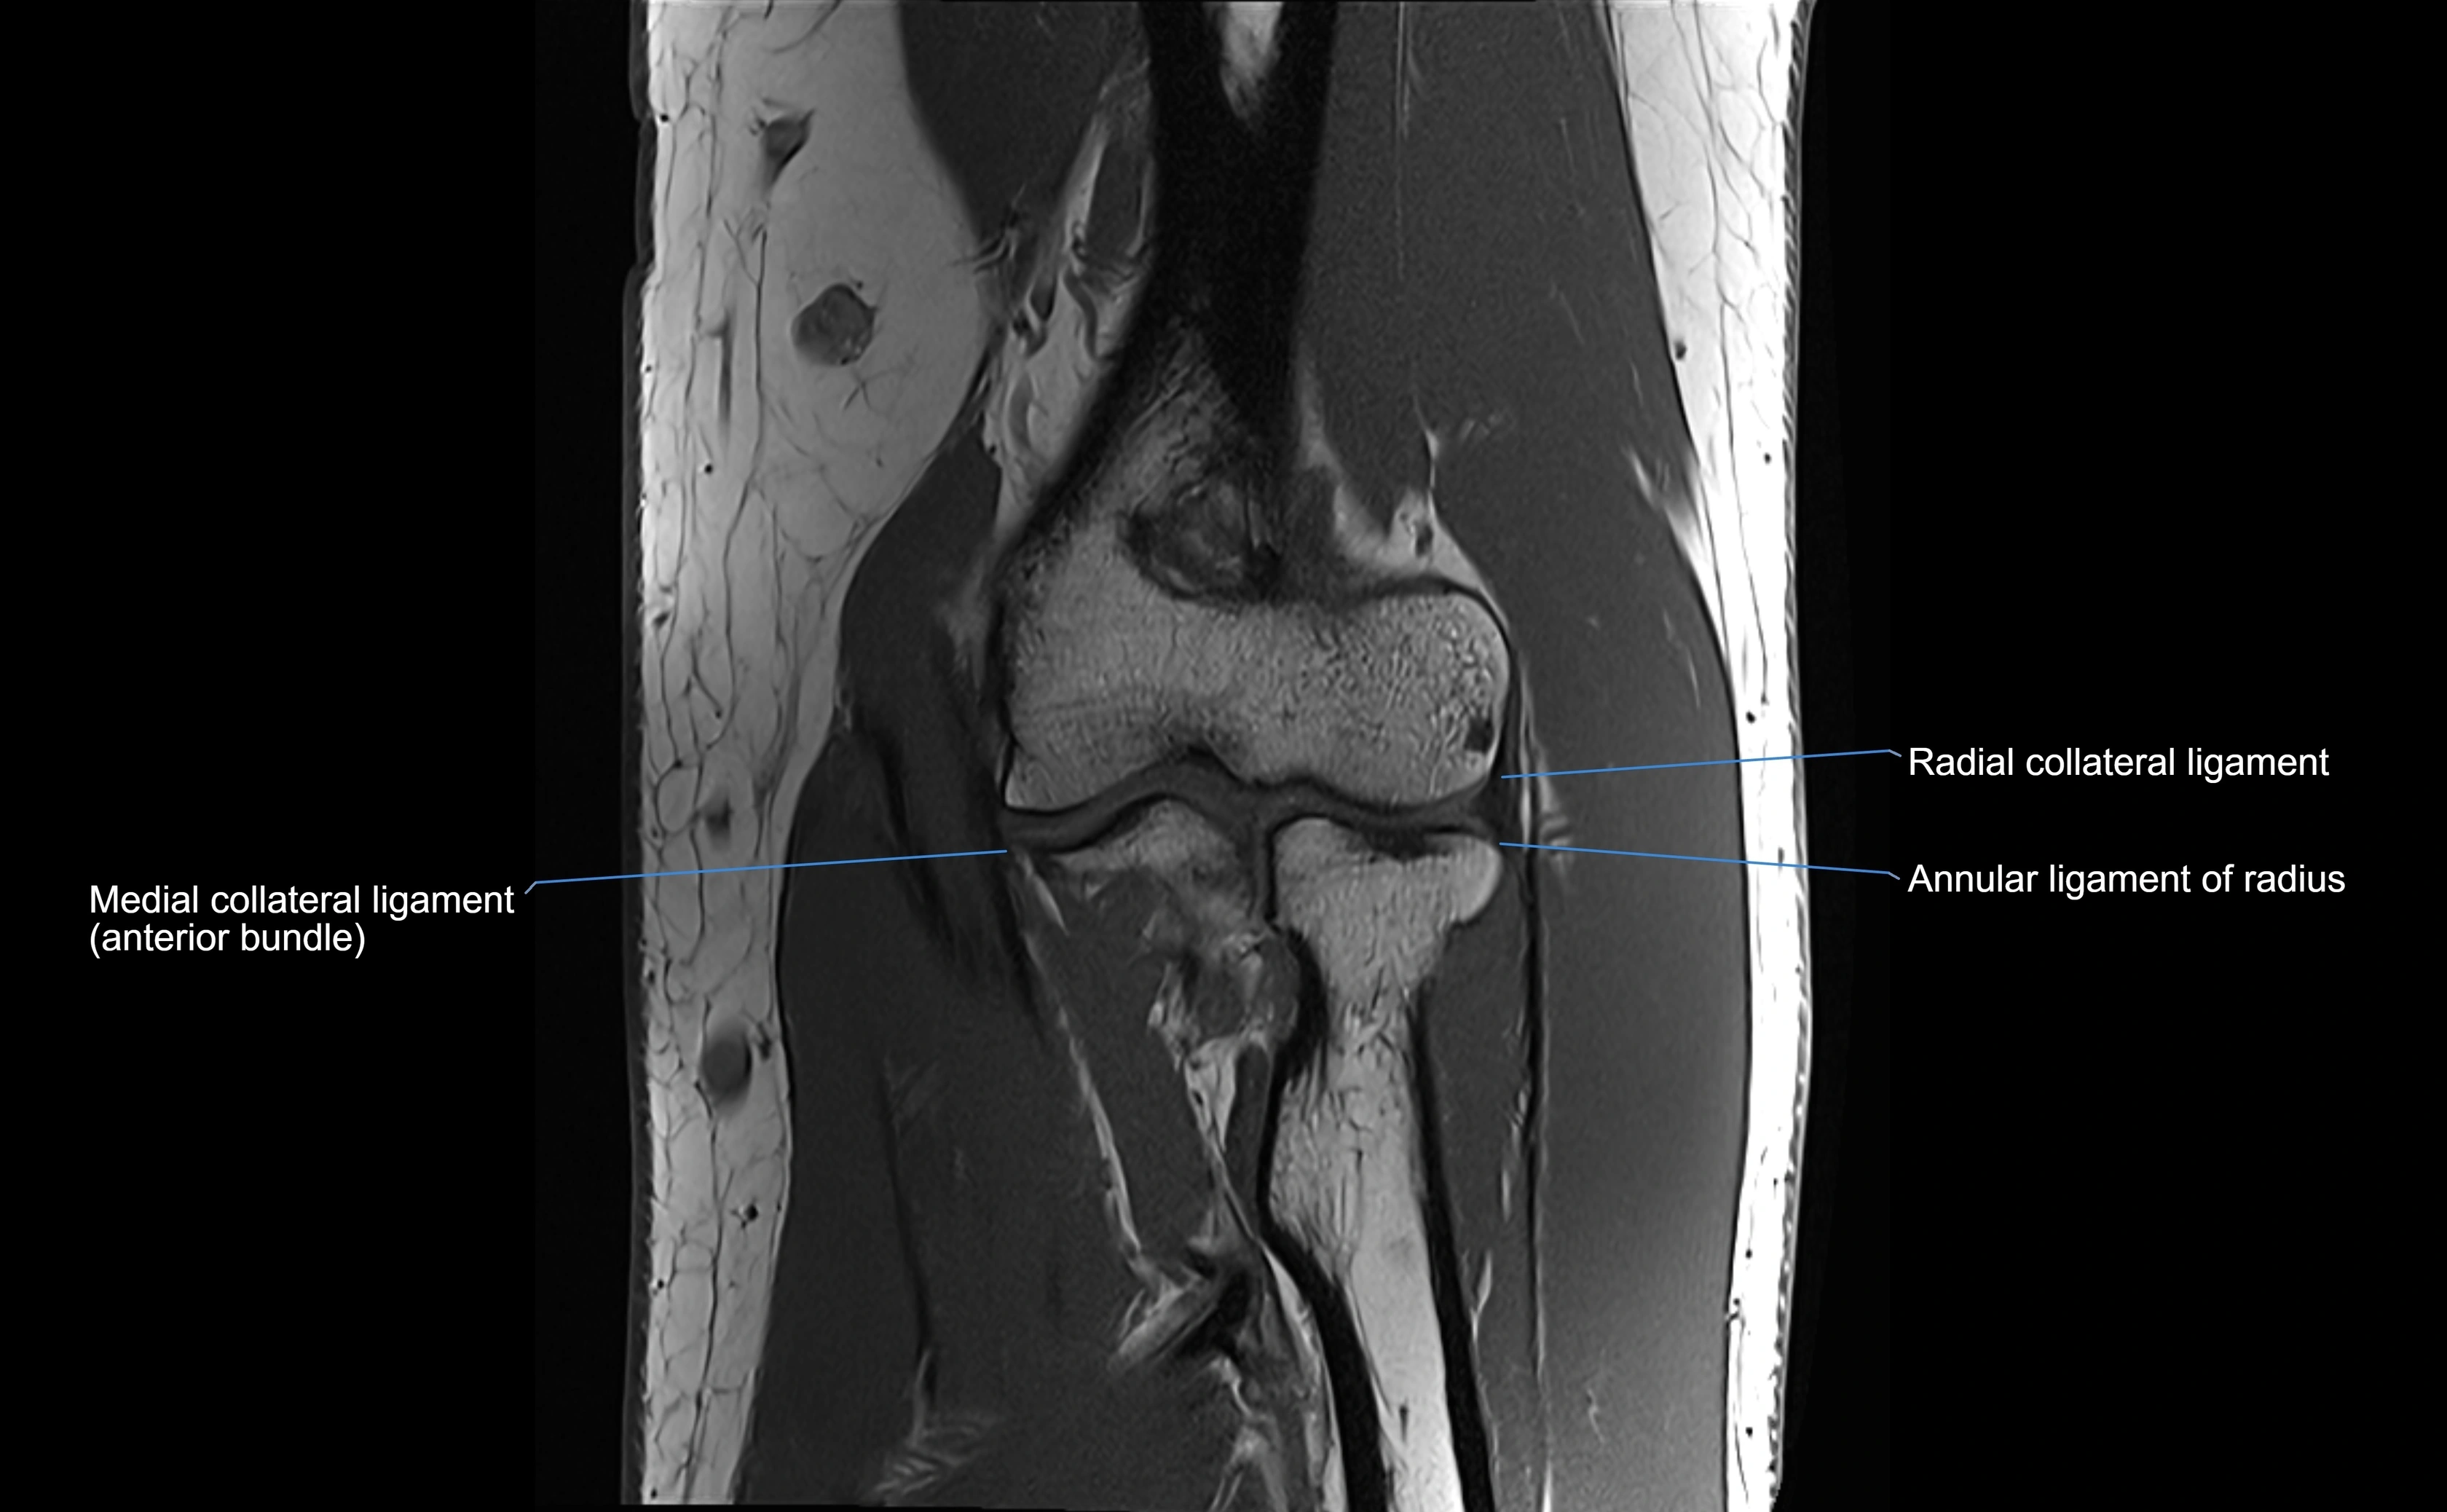

MRI images

image